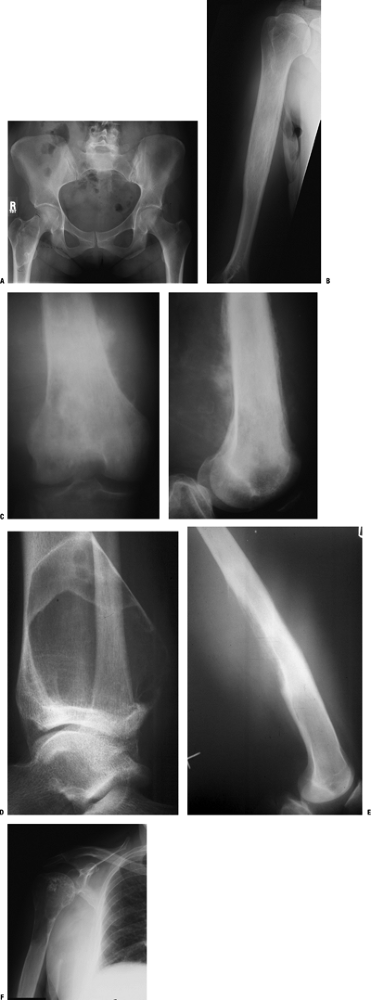

Figure 1-12 Bone lesions with a spectrum of responses in the surrounding bone. (A) A proximal femoral fibrous dysplasia lesion shows marginal sclerosis. (B) A humeral diaphyseal region of cortical thickening is seen here in association with an area of chronic osteomyelitis. (C)

Poorly organized new bone formation demonstrating both Codman’s

triangle and a sunburst appearance is shown here in an osteosarcoma. (D) Periosteal neocortical response is seen in the posterior cortex of the distal tibia due to this aneurysmal bone cyst. (E) Onion-skinning periosteal reaction with Codman’s triangle and an associated soft tissue mass is shown in this Ewing sarcoma. (F) Endosteal expansion and erosions are seen with this low-grade chondrosarcoma.Table 1.7 Patterns of Mineralization Within Bone LesionsDescription Typical Lesions Other Distinguishing Features Radiolucent (lytic) Absence of matrix Numerous (nonspecific) Numerous Mineralized Calcified Punctate rings and arcs Hyaline cartilage lesions*

Figure 1-13 Bone lesions with a spectrum of types of matrix mineralization. (A) Absence of matrix mineralization is seen in a lucent lesion from a unicameral bone cyst. (B) The typical rings and arcs of hyaline cartilage matrix mineralization are seen in this metacarpal enchondroma. (C) The same type of hyaline cartilage matrix mineralization is apparent in this chondrosarcoma. (D) Ground glass appearance is typical of fibrous dysplasia, as in this lesion of the proximal radius. (E)

A mixed sclerotic and partially lytic lesion of the proximal femur,

which is frequently seen in the setting of metastatic breast cancer. (F) Densely sclerotic metastases are the most common appearance in bony metastatic prostate carcinoma. (G)

Lytic metastases are the most common appearance for metastatic lung

cancer, which is also the most common primary source for metastases

distal to the elbows and knees, as shown in this tarsal navicular

metastatic deposit from lung carcinoma. (H) A cumulus cloud pattern of matrix mineralization is most characteristic of osteosarcoma.Table 1.8 Multifocal Bone LesionsPediatrics Adults Metabolic bone diseases Multifocal Paget’s disease of bone Infections Chronic recurrent multifocal osteomyelitis Malignant neoplasms Metastases (neuroblastoma, rhabdomyosarcoma, osteosarcoma)